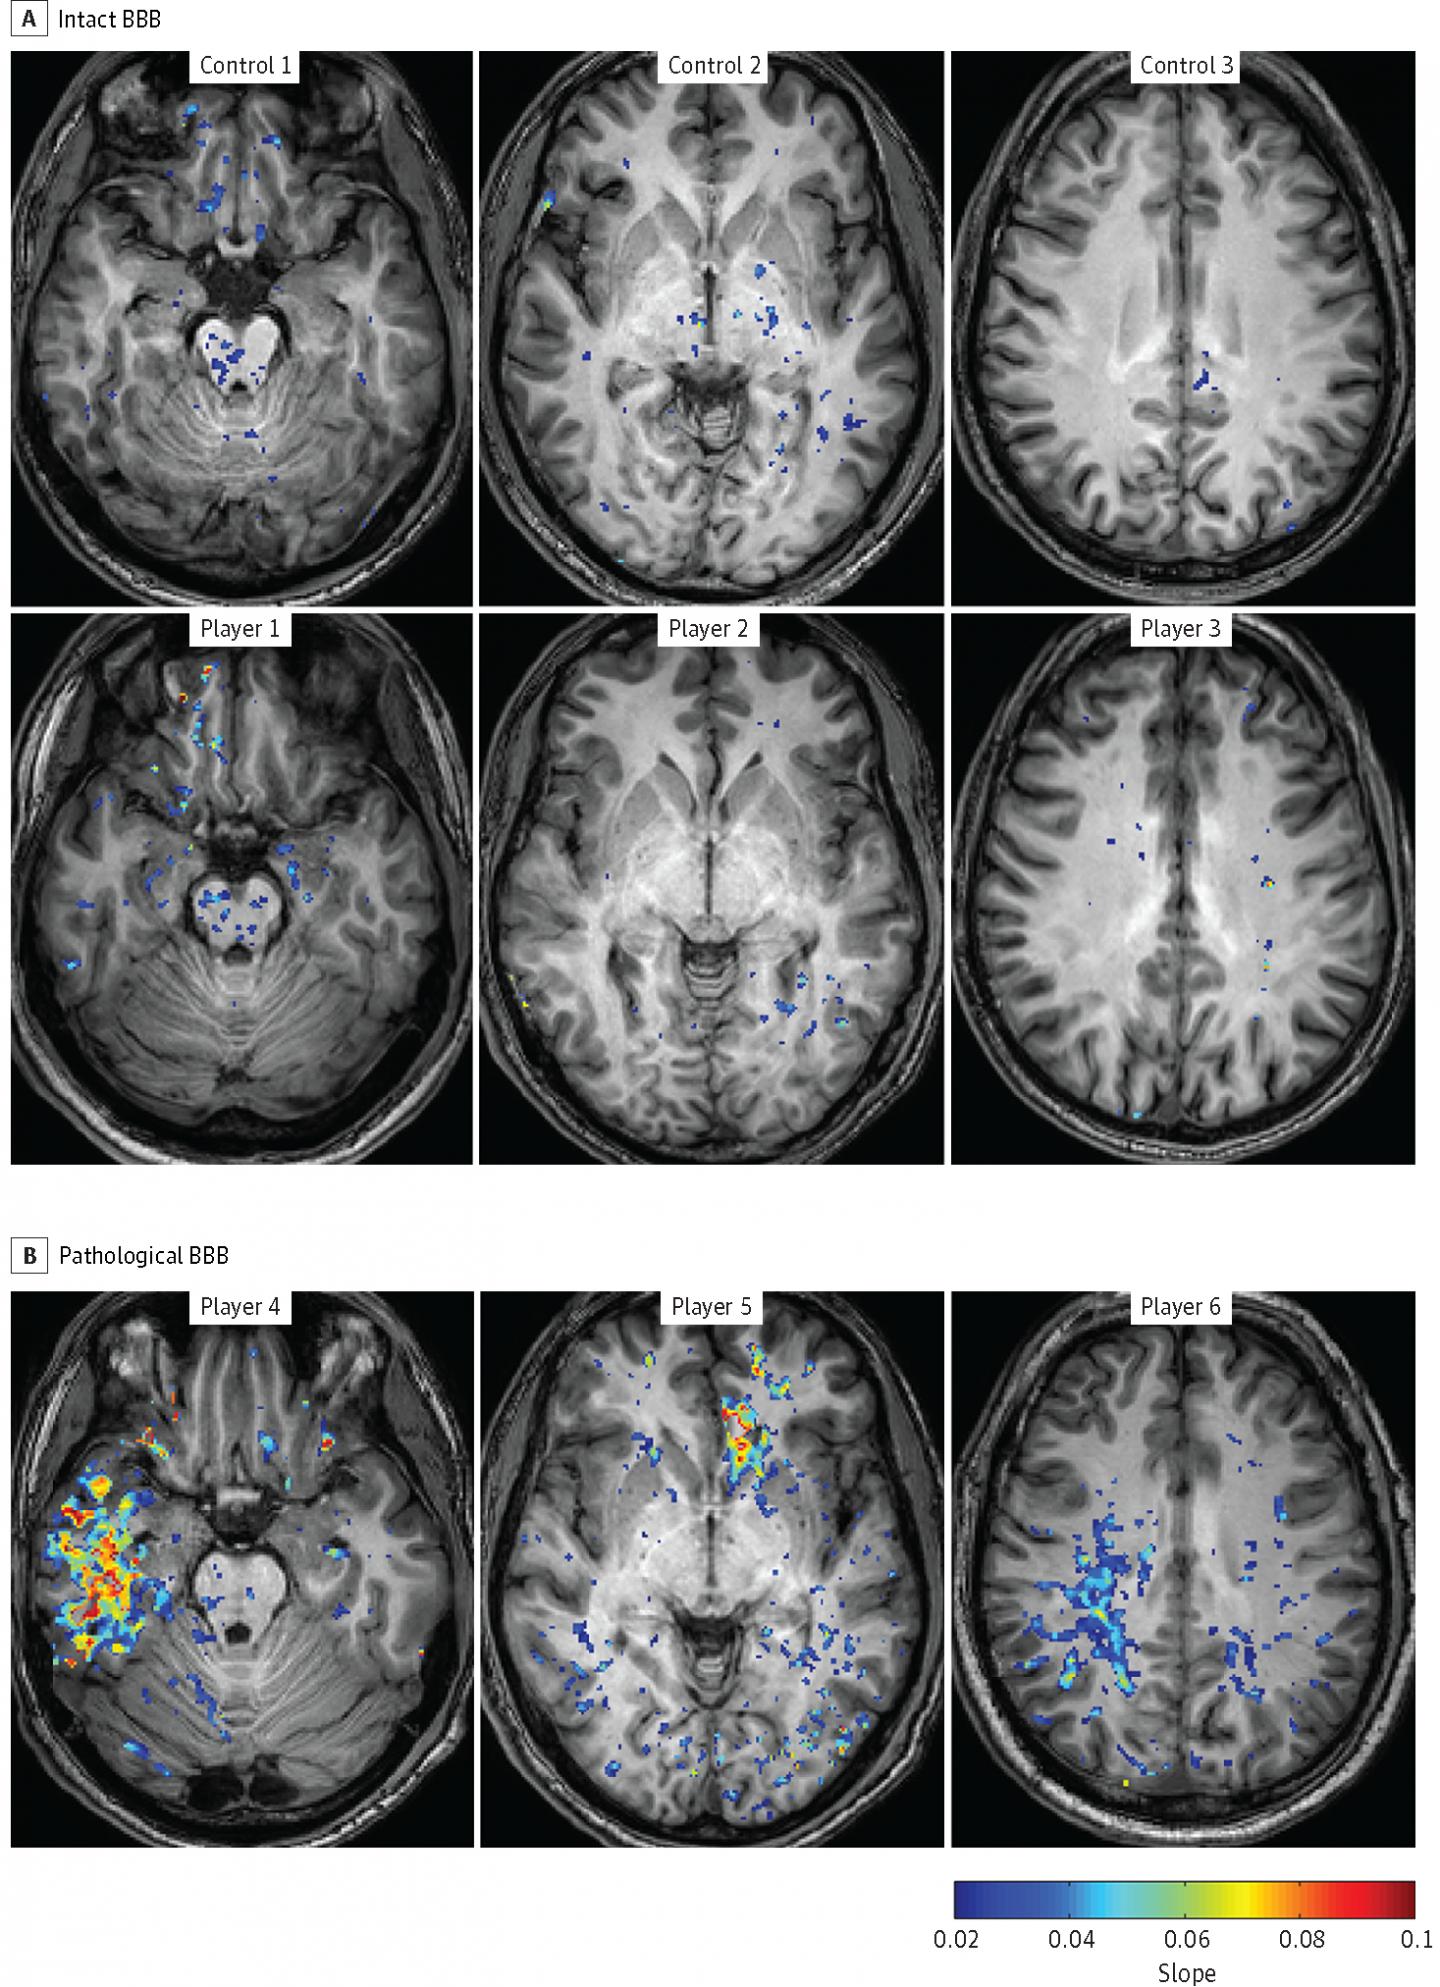

image: The images from the Ben-Gurion University of the Negev JAMA Neurology study represent Blood-Brain Barrier (BBB) Permeability in Football Players vs. a control group. The players in the pathological-BBB group presented focal BBB lesions in different cortical regions including the temporal (player 4), frontal (player 5), and parietal (player 6) lobes. Both gray and white matter were involved. view more

"The goal of our study was to use our new method to visualize the extent and location of BBB dysfunction in football players using Dynamic Contrast-Enhanced Magnetic Resonance Imaging (DCE-MRI) on a Phillips 3-T Ingenia. Specifically, it generates more detailed brain maps showing brain regions with abnormal vasculature, or a 'leaky BBB.' "

The DCE-MRIs were given between games during the season and revealed significant damage. Forty percent of the examined football players with unreported concussions had evidence of "leaky BBB" compared to 8.3 percent of the control athletes.

"The group of 29 volunteers was clearly differentiated into an intact-BBB group and a pathological-BBB group," Friedman explains. "This showed a clear association between football and increased risk for BBB pathology that we couldn't see before. In addition, high-BBB permeability was found in six players and in only one athlete from the control group."